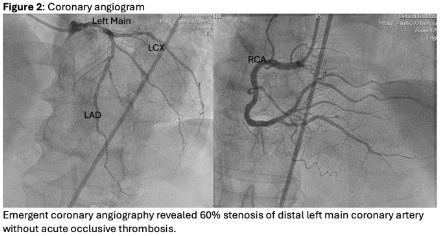

A 76-year-old male presented with 3 days of chest pain and infero-lateral ST elevations (Figure 1). Emergent cardiac catheterization revealed 70% calcified left main disease without plaque rupture or thrombus (Figure 2). IVUS confirmed stable disease. Echocardiogram showed LVEF 45%; an intra-aortic balloon pump (IABP) was placed, and surgery was deferred pending ticagrelor washout. Over the next 3 days, the patient’s condition worsened with rising troponin, LVEF decline to 10%, right ventricular failure, and complete heart block. The clinical picture was inconsistent with coronary anatomy, prompting suspicion for myocarditis. Endomyocardial biopsy and temporary pacing were performed. Due to worsening cardiogenic shock, mechanical circulatory support with Impella 5.5 was initiated. Immediately after Impella, the patient developed ventricular tachycardia and suction alarms due to right sided failure, therefore a veno-arterial Venoarterial Extracorporeal Membrane Oxygenation (ECMO) was initiated. Biopsy confirmed lymphohistiocytic myocarditis with immunophenotype supported the diagnosis of tuberculous myocarditis (Figure 3); respiratory cultures grew Mycobacterium tuberculosis. Despite treatment with corticosteroids, IVIG, inhaled nitric oxide, and antitubercular treatment, the patient failed to improve and expired.